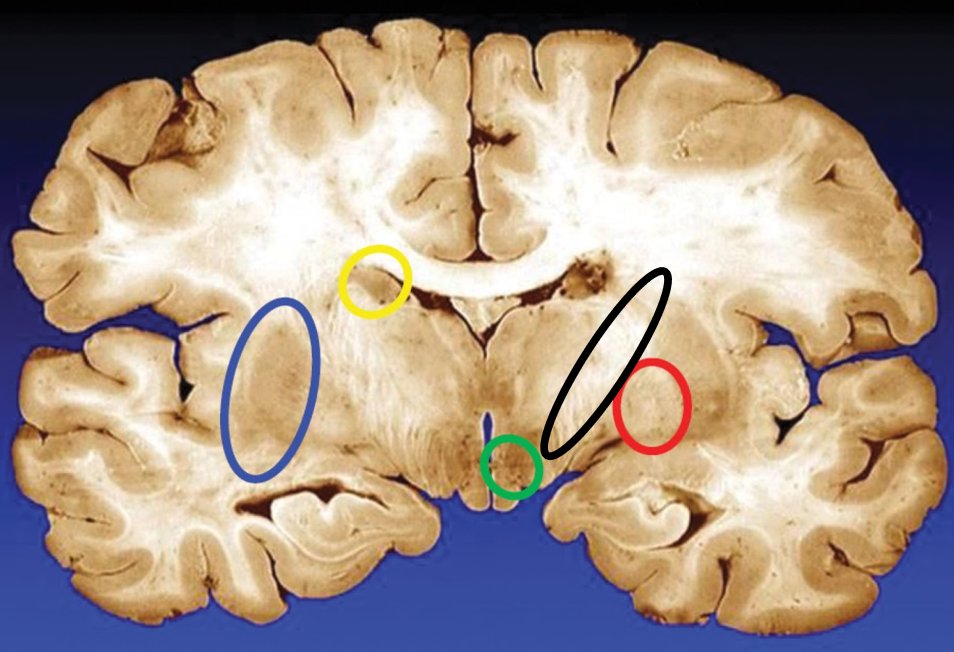

blue

putamen

yellow

caudate

green

subthalamic nuclei

black

internal capsule

red

globus pallidus